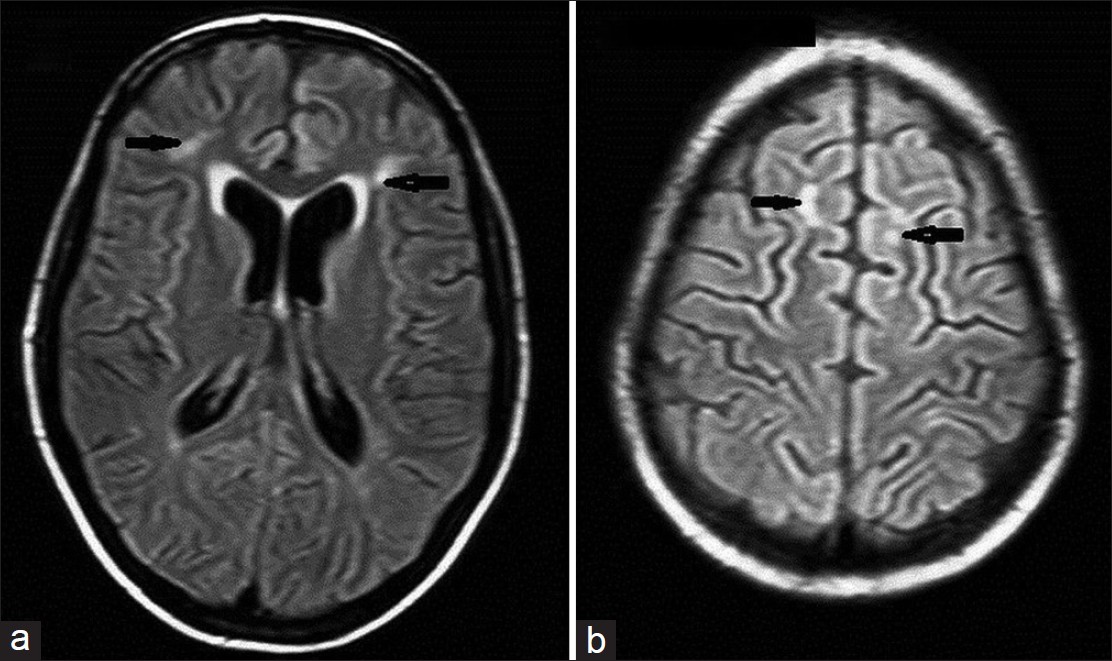

واخذ يراقب يداها المرتعشة وهي ترسم الدائرة ولاحظ انها وضعت كل الارقام في الجهة اليمنى من الدائرة وهنا فهم الطبيب ان لديها خلل في الشق الايسر من دماغها الذي يسيطر على نصف جسمها الايمن

3.وهذا مرض نادر تهاجم فيها جسيمات مضادة نظم المناعة وتتسبب بالتهاب الدماغ وهذه الجسيمات سميت Anti Nmda